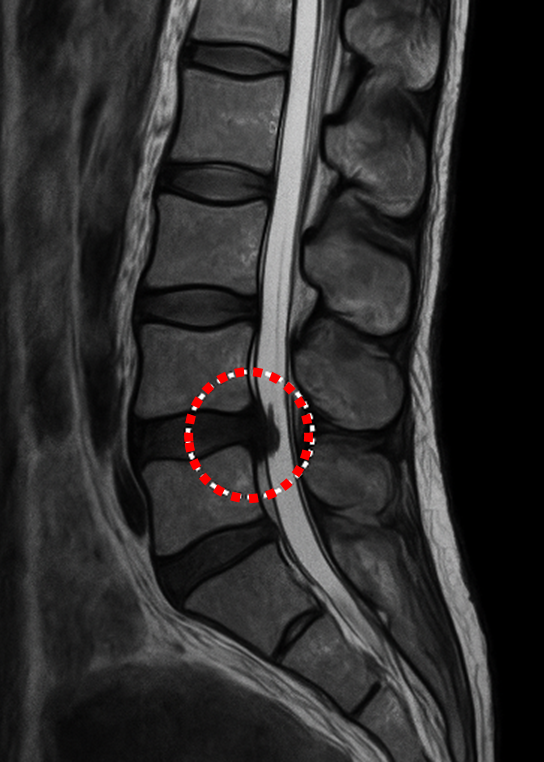

○背骨や脳の検査

MRIは、脳梗塞や脳腫瘍、手足や背骨などの整形外科領域に優れています。